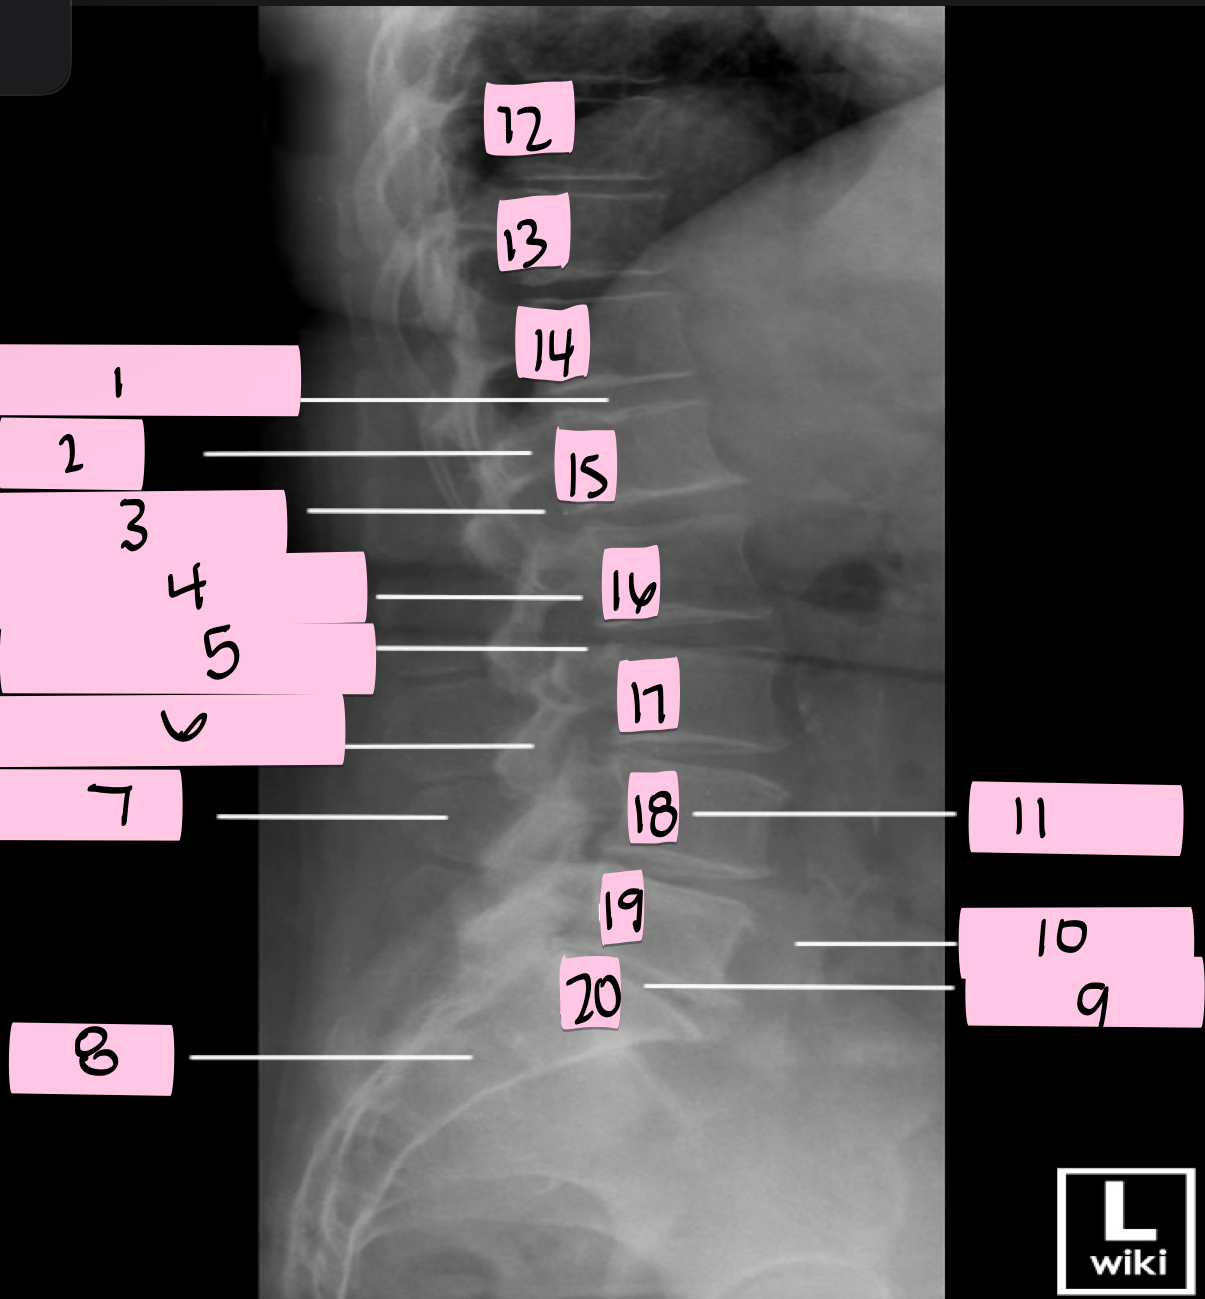

What is 1 pointing to?

Transverse process

What is 2 pointing to?

Intervertebral disk

What is 3 pointing to?

Ala of sacrum

What is 4 pointing to?

Sacrum

What is 5 pointing to?

12th Rib

What is 6 pointing to?

Pedicle

What is 7 pointing to?

Spinous process

What is 8 pointing to?

Psoas muscle

What is 9 pointing to?

Lumbar body (L4)

What is 10 pointing to?

Sacroiliac joint